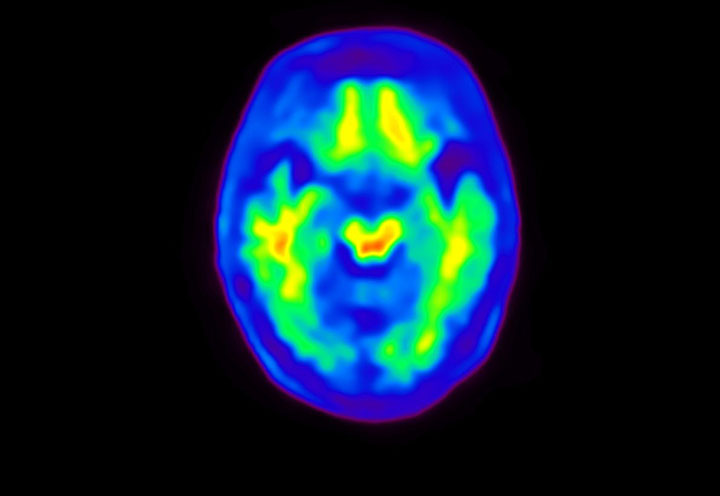

Axial